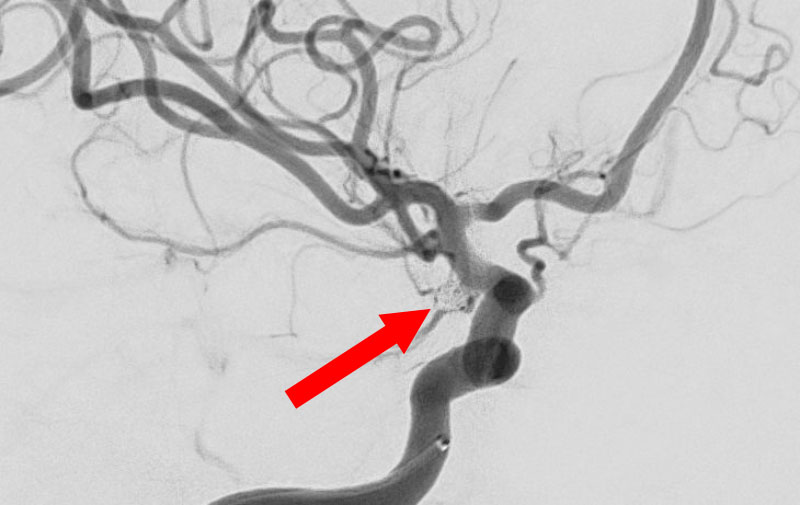

No.1596 手術前

くも膜下出血

左中大脳動脈瘤破裂

40代